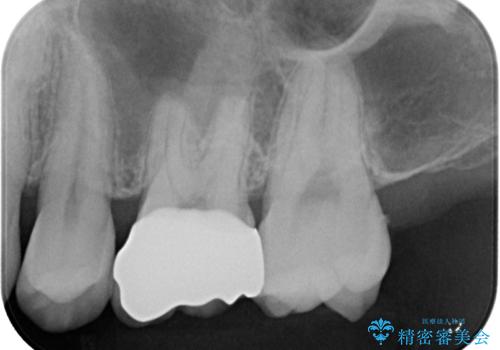

歯と歯茎の間に圧排糸と言われる糸を入れてシリコーン印象材にて型どりをしました。

違和感が全くないと喜んでいただきました。